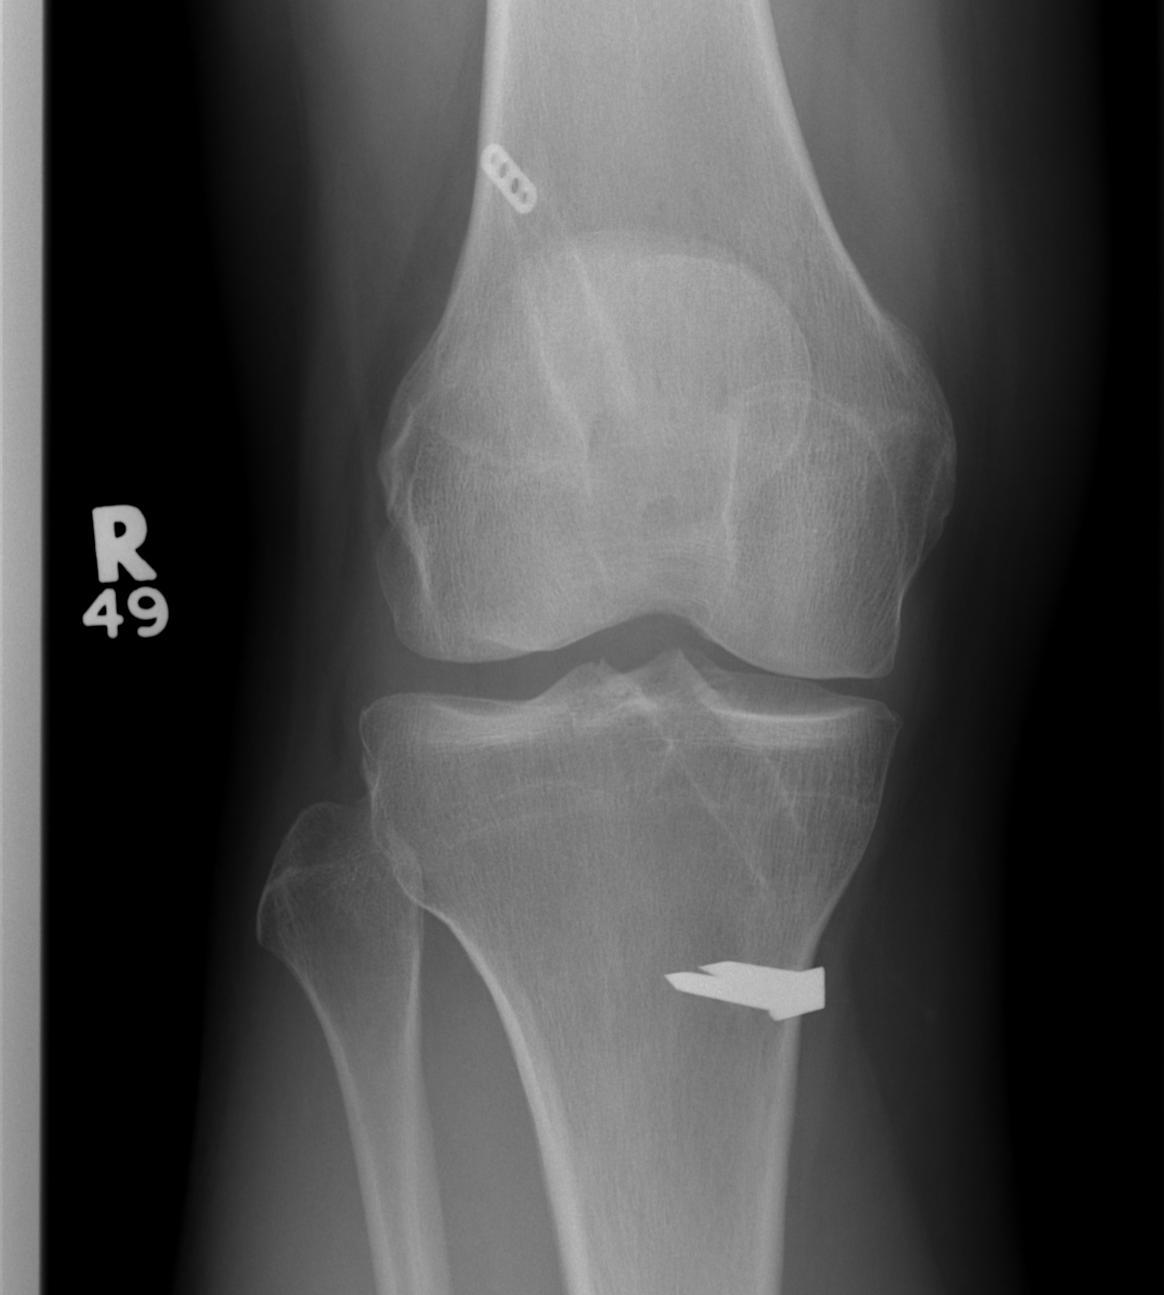

Case 1

Patient with traumatic failure ACL, previous hamstring with endobutton and bioabsorbable screw

Graft likely too vertical, evidence of tibial tunnel lysis

Old staple had to be removed. Graft passed and fixed on femoral side with 9 x 25 mm screw.